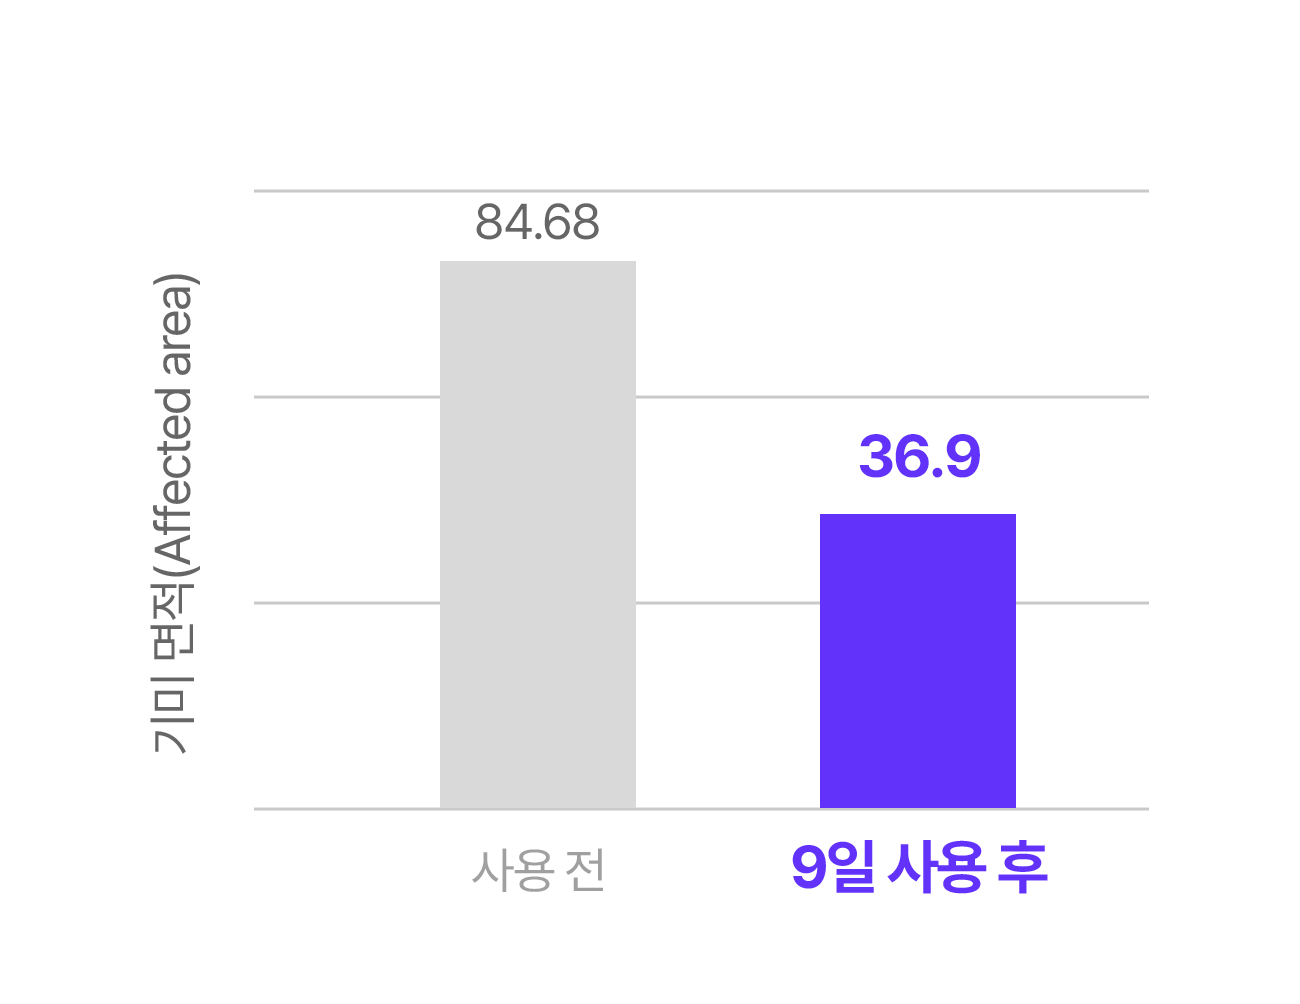

A. 실제 임상 실험과 소비자 테스트 결과, 피부톤 개선과 잡티 완화에 있어 9일 안에 변화를 체감한 사용자가 많았습니다. 물론 개인 피부 상태에 따라 차이는 있을 수 있으나, 빠른 효과를 목표로 설계된 제품입니다.